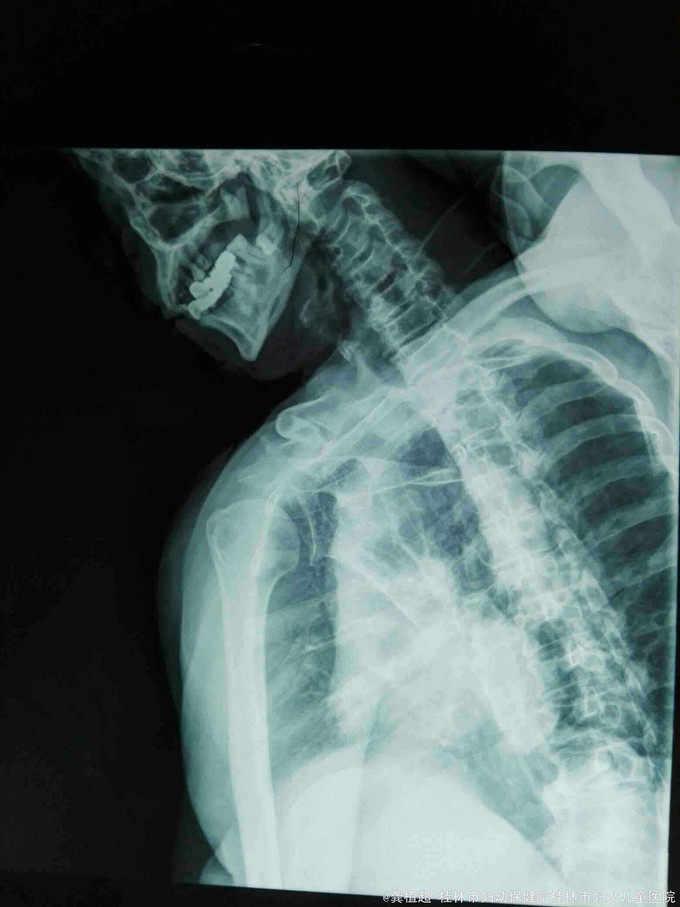

主诉:右肩外伤后疼痛、活动受限27天。 现病史:患者于2015年9月12日不慎跌倒右肩部先着地,右肩部剧烈疼痛、活动受限。肢体无麻木。在家自行外敷草药,症状无缓解。于2015年9月15日到我院门诊行X线检查提示右侧肩关节脱位。门诊予徒手复位术,疼痛明显缓解。术后复查X线示右肩关节复位良好,但患者诉右肩关节仍不能活动,同时伴有右小指麻木,第3、4指伸直受限。近3日上症加重遂来我院,行右上肢肌电图检查提示‘右侧臂丛神经损伤’,予收住院进一步诊治。饮食、睡眠、二便正常。

脊柱无明显畸形,各椎体无明显压、叩痛;右侧上臂近段前侧肿胀明显,右侧肩关节无压痛。右侧肩关节被动活动可,右侧三角肌肌力I级,其余右上肢肌群肌力约Iv级,右侧肩关节不能主动外展及前屈,右侧三角肌区皮肤及右手小指肌小鱼际肌部位浅感觉迟钝。肢端血运良好。

右侧臂丛神经损伤(腋神经、尺神经)